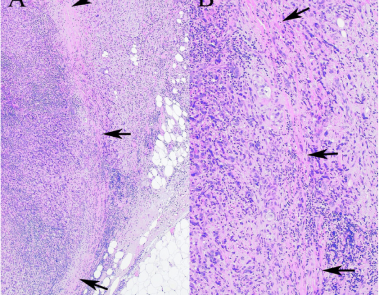

AngolAz őrszemnyirokcsomó extracapsuláris áttétének jelentősége az emlőrák sebészi kezelésében

MagyarA mammaria interna őrszemnyirokcsomó biopsziával szerzett tapasztalataink